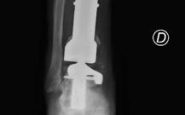

Alla diagnosi è seguita la resezione del tumore con impianto di una mega-protesi di tibia prossimale, cioè nell'area vicino al ginocchio. Dopo circa un anno dall'intervento, però, una grave infezione della protesi impiantata ha costretto Mario a subire una serie di complessi interventi chirurgici che si sono conclusi con l'impianto di una protesi totale di gamba e di caviglia in titanio, rivestita in argento per evitare nuove infezioni.

Ma ancora non era finita. A distanza di 6 anni, Mario torna dagli ortopedici del Gemelli per un dolore alla caviglia. Gli esami rilevano la rottura di una vite della protesi, a livello della caviglia. E' necessario sostituire il pezzo, ma l'unico modo per farlo – decretano gli specialisti – è facendo confezionare una protesi 'custom-made', disegnata e realizzata su misura. Gli ortopedici del Gemelli inviano perciò la Tac di Mario all'Implantcast, una ditta specializzata di Buxtehude, cittadina a sud ovest di Amburgo, in Germania. Basandosi sulla ricostruzione tridimensionale della caviglia bionica di Mario, i bioingegneri realizzano un calco della protesi custom-made con una stampante 3D, sul quale viene realizzata la protesi in titanio per l'impianto definitivo. Ed ecco l'intervento effettuato da Carlo Perisano, professore aggregato dell'Università Cattolica del Sacro Cuore e dirigente medico presso la Uoc di Ortopedia e Traumatologia della Fondazione Policlinico Gemelli, diretta da Giulio Maccauro. L'operazione dà i suoi frutti: "A distanza di appena qualche giorno dall'intervento, Mario sta di nuovo in piedi sulla sua gamba bionica arricchita di quest'ultimo gioiello tecnologico", riferiscono dall'Irccs capitolino.

"Il paziente – afferma Perisano – era stato sottoposto negli anni a diversi interventi chirurgici per il trattamento di un tumore osseo della tibia e delle successive complicanze che avevano compromesso anche le articolazioni del ginocchio e della caviglia. Nel 2019 è stato sottoposto a posizionamento di mega-protesi custom-made personalizzata di tibia totale ginocchio e caviglia, scongiurando così il rischio di una chirurgia demolitiva, ovvero dell'amputazione dell'arto, garantendo al paziente il ritorno alle normali attività quotidiane".

"Le protesi personalizzate (o custom-made) – illustra lo specialista – rappresentano un'innovazione significativa in ambito ortopedico. Si tratta tuttavia di impianti costosi, proprio perché realizzati su misura, che vengono per questo riservati a casi particolari e selezionati. L'impiego di tali protesi ci consente di personalizzare l'intervento sulle specifiche esigenze del paziente, garantendo un'accurata riproduzione anatomica ed un elevato grado di recupero funzionale. Nel caso specifico, la realizzazione di una componente astragalica su misura ci ha consentito di revisionare l'attuale protesi di caviglia e ha permesso al paziente un precoce ritorno ad un livello funzionale normale". E dal Gemelli rimarcano che "la revisione con una protesi di caviglia custom made di una protesi totale di caviglia e tibia è un intervento finora mai descritto in letteratura".